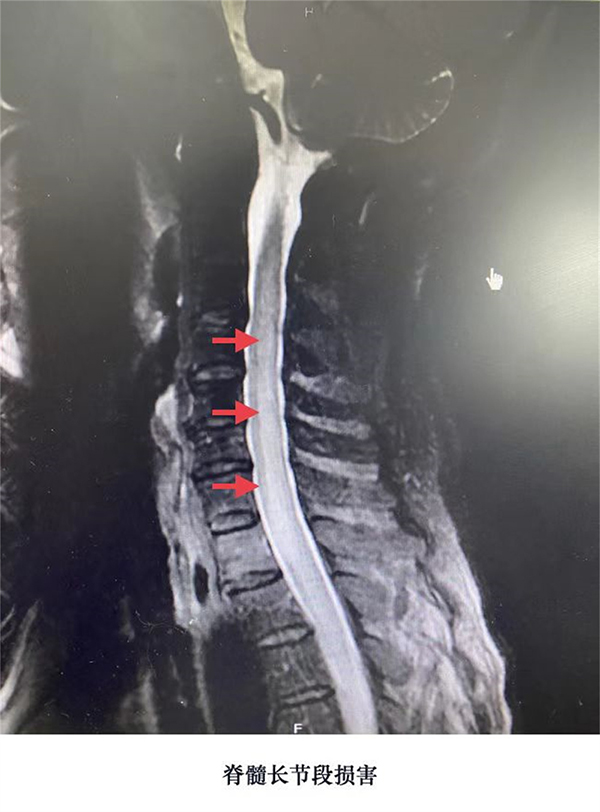

周主任详细询问病史及查体,看了外院胸椎核磁胸髓的异常信号,认为患者的“呕吐”和“脊髓的异常信号”有可能是一种神经科疾病引起,有多种相关神经疾病需要鉴别诊断。于是,尽快安排患者住院,周卫东主任带团队查房,立即安排眼科会诊,同时进行颈椎、胸椎核磁及腰穿、宏基因等相关检查。结果提示患者明显的视力下降、颈髓、胸髓多节段的异常信号,脑脊液白细胞数、蛋白含量增高,血和脑脊液免疫相关抗体阴性,脑脊液见寡克隆区带;水通道蛋白抗体检测阴性,考虑脱髓鞘疾病(播散性脑脊髓炎、视神经脊髓炎谱系疾病等),脑脊液宏基因检查排除微生物直接感染导致的炎性疾病。按照脱髓鞘疾病治疗,呕吐症状很快好转,常规的磁共振未发现明确的极后区病变,经影像科会诊协调,加做T2 Flair矢状位的头核磁共振,进一步证实T2 Flair矢状位极后区病变。多条证据支持诊断为“以极后区为首发症状的视神经脊髓谱系疾病”。给予激素等相应治疗,一周后患者不再呕吐了,视力明显恢复(0.2到1.0)了,可以重新站起来了,半个月后在室内行走自如。

周卫东主任介绍,视神经脊髓炎谱系疾病(NMOSD)是一种自身免疫介导的以视神经和脊髓受累为主的中枢神经系统炎性脱髓鞘疾病。好发于青壮年,临床上多以严重的视神经炎和纵向延伸的长节段横贯性脊髓炎为主要临床特征。包含视神经炎、急性脊髓炎、极后区综合征、急性脑干综合征、急性间脑综合征和大脑综合征。